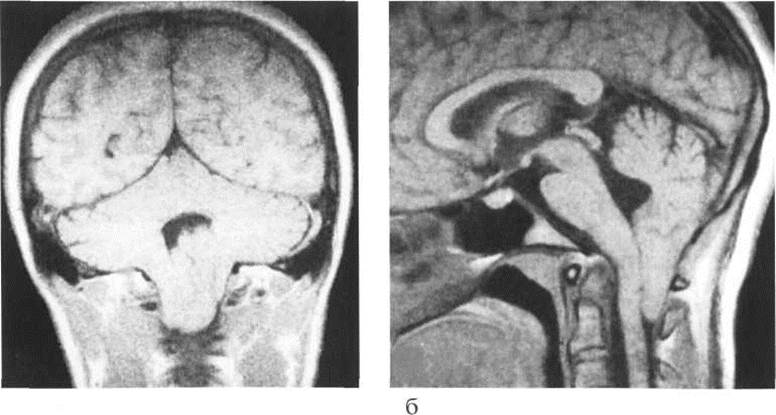

Аномалия Арнольда-Киари: MRI снимки